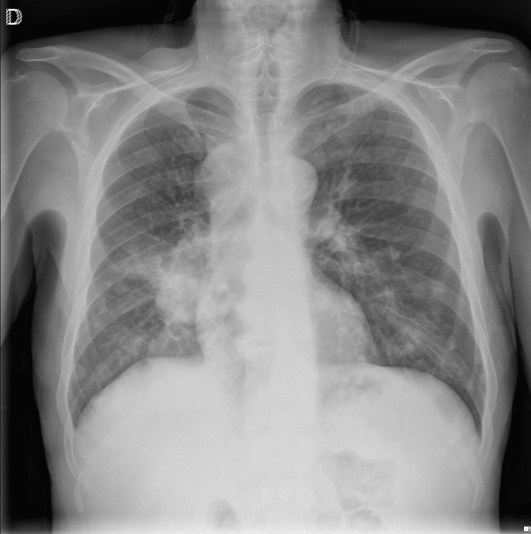

CASO: Febrícula y tos de 4 días de evolución.

Hallazgos:

- En la placa PA se observa una asimetría en los hilios pulmonares, el hilio izquierdo tiene una densidad aumentada.

- Tras examinar la placa lateral se observa un aumento de densidad en la columna que puede ser compatible con una condensación, es el signo de la desnificación vertebral.

SIGNO DE LA DENSIFICACIÓN VERTEBRAL: En la radiografía lateral normal, la densidad de la columna torácica tiende a disminuir desde la parte superior hasta el diafragma; la alteración de ese patrón por la presencia de una densidad superpuesta a la columna, indica la existencia de una consolidación pulmonar. Este signo adquiere especial valor cuando en la proyección posteroanterior la consolidación está oculta en el espacio retrocardíaco o en la base pulmonar.